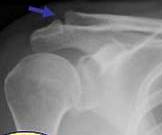

ENTORSA ACROMIOCLAVICULARA

Comparatie cu aspectul normal al articulatiei→

Radiografic- aspect normal →